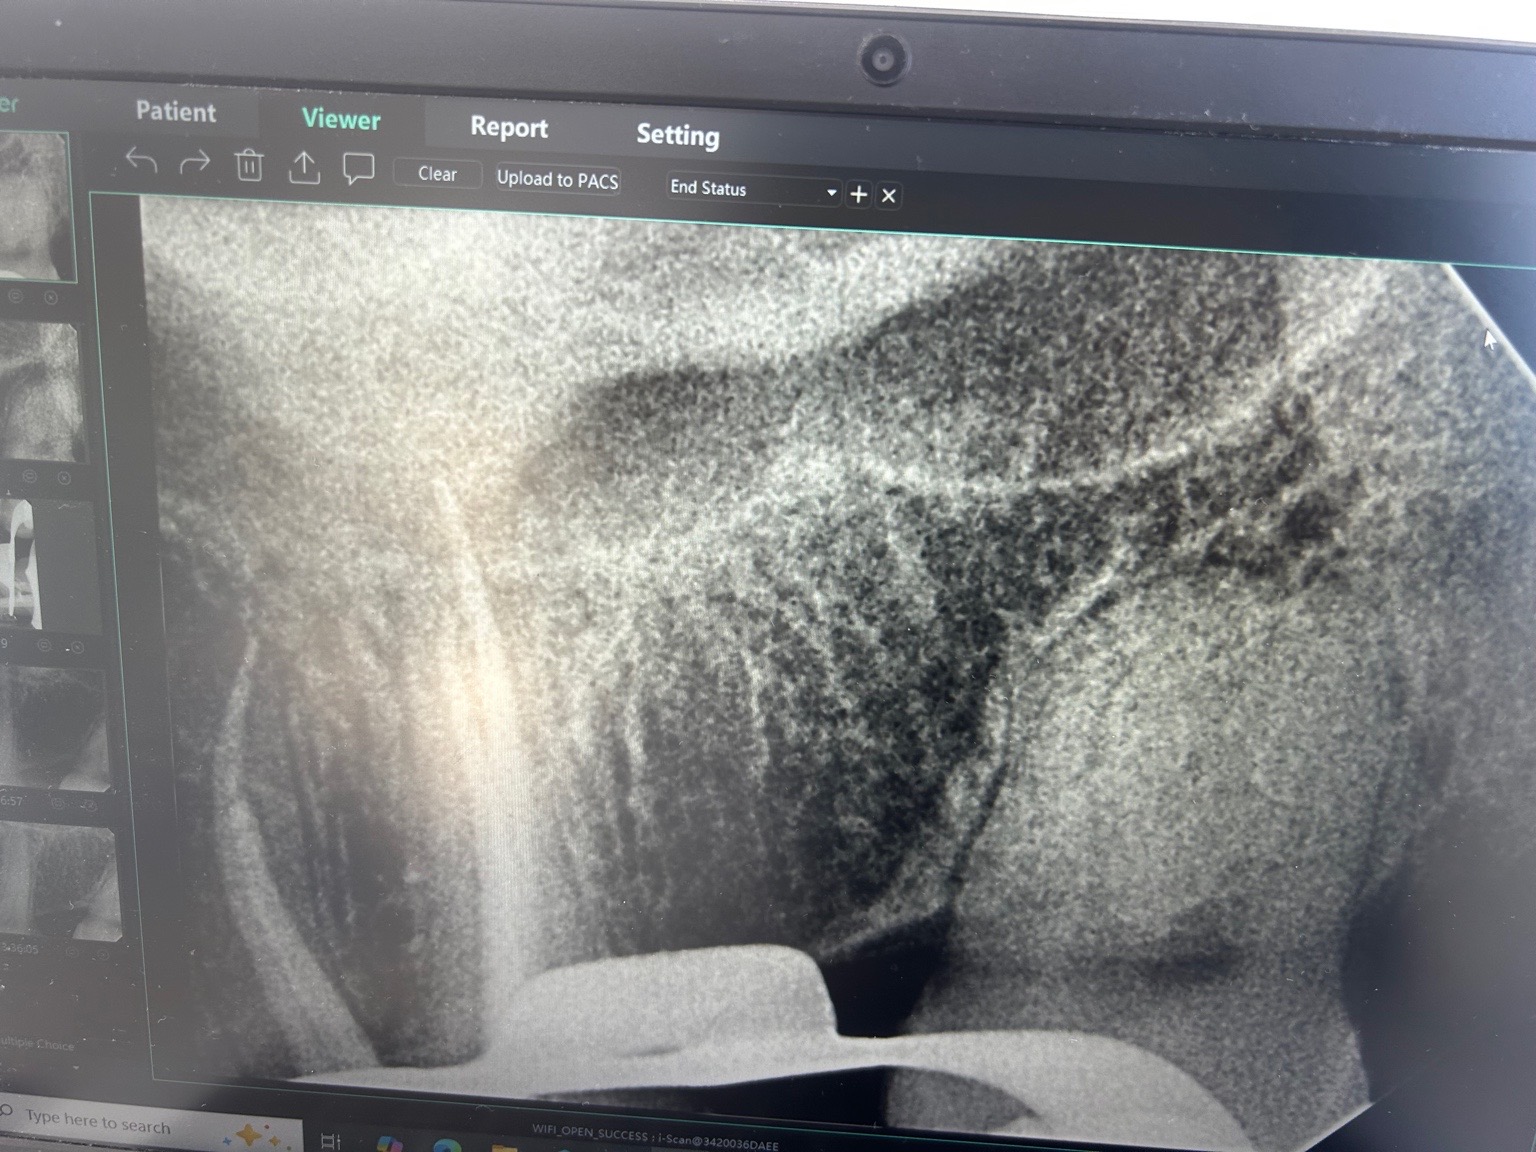

Uiteindelijk was ik in het buitenland en kreeg ik weer last. Uiteindelijk cbtc scans gedaan en microscopisch 4 kanalen. Was heftig lang. Geen verticale fracturen gevonden maar wel gevuld met glasvezel stiften. Dame werkte bij alldent in Frankfurt. Kroon vond ze met huidige stand niet nodig maar goed. Even je objectieve mening wat vindt je er van?. Ze was extreem secuur. Napijn wel met bijten maar was vanwege grote behandeling gebruikelijk. Kan nog even zeuren. Laesie was minimaal volgens haar.

Ja die indruk kreeg ik ook. Nu inderdaad afwachten. Was is hier nu meestal het proces wanneer je zegt afwachten. Ontsteking moet minder worden etc? Op de foto vond ze die minimaal maar de pulpa was al langer afgestorven. Dat afwachten is het heel proces?